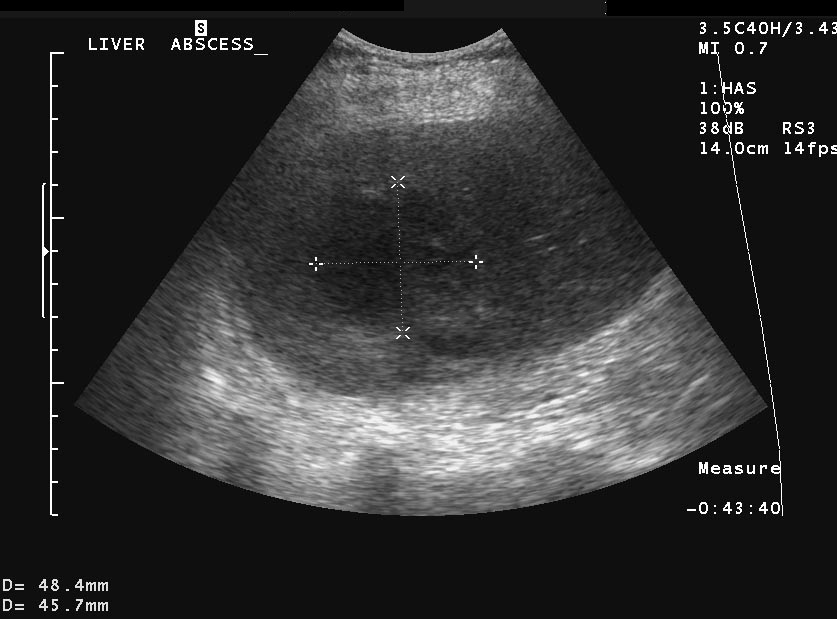

Liver abscess can develop either following the severe inflammation of the biliary ducts and the gallbladder or following a tumorous necrosis or by the spread of an external inflammation to the liver. By the help of the US, a cystic lesion can be seen with multiple internal echos containing gas bubble frequently as well. In order to determinate the further therapy, contrast enhanced CT examination can be needed, if the US imaging of the entire liver was not possible. An avascular intrahepatic lesion can be seen well on the CT with a contrast enhancing wall (sometimes multifocal as well) (Figure 30). An US or CT guided percutaneous drainage can provide a therapeutic result depending on the lesion's size and location (Figure 31).

Figure 31: Abscess in the liver, US control after US guided drainage